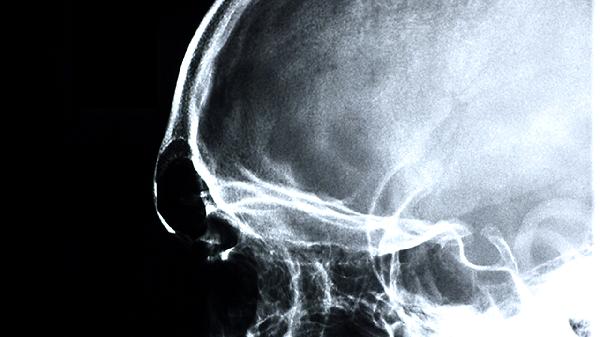

脑供血不足可以吃阿司匹林吗

脑供血不足患者一般可以遵医嘱服用阿司匹林,但需严格评估出血风险。阿司匹林具有抗血小板聚集作用,常用于预防缺血性脑血管事件。

脑供血不足多由动脉粥样硬化导致血管狭窄引起,阿司匹林能抑制血小板聚集,减少血栓形成概率,从而降低脑梗死风险。对于存在高血压、糖尿病等危险因素的患者,医生可能建议长期小剂量服用阿司匹林肠溶片进行二级预防。服药期间需定期监测凝血功能,观察有无牙龈出血、皮下瘀斑等不良反应。合并胃溃疡或消化道出血病史者需联用质子泵抑制剂保护胃肠黏膜。